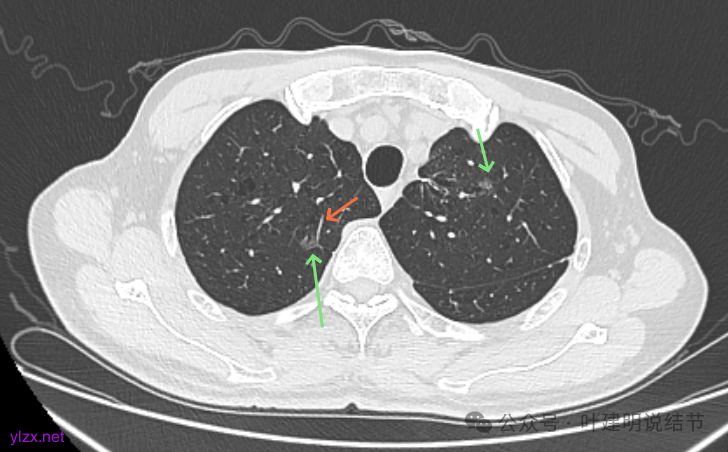

右上冠状位显示病灶纯磨,血管进入穿行,灶内空泡征,表面毛刺征,没有明显实性成分。

左上病灶冠状位显示纯磨,部分连续细毛刺,灶内有扩张的细支气管似的,整体轮廓清。

矢状位见右上病灶也是纯磨,灶内的血管可见,表面部分有细毛刺,整体轮廓与边界清楚。

左上病灶矢状位见也是纯的,没有实性成分。

右肺尖磨玻璃结节持续存在,随访有所进展,中间伴空泡征,也有微小血管贴边以及进入,整体轮廓与边界清楚,要考虑是肿瘤范畴的,从影像来看目前大概是原位癌或微浸润性腺癌可能性大;左肺尖的也是磨玻璃密度的,不太纯,有少许偏实性成分,轮廓较清,边缘不光滑,也有小空泡,考虑是肿瘤范畴的,综合大小形态与密度来看,以不典型增生或原位癌可能性较大。由于两处目前风险均仍说不上多大,还是磨玻璃密度为主的,且左侧又已经手术过,个人倾向保守点,仍可9-12个月复查随访,如果随访进展并风险增加到该处理了,届时右侧可考虑单孔胸腔镜下楔形切除,左侧的稍倾向于消融处理。意见供参考!